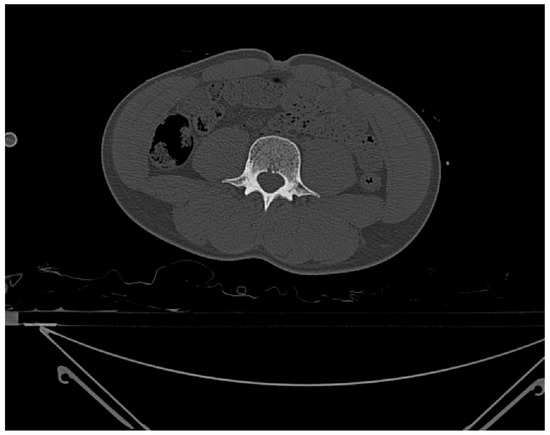

Figure 3.

CT slice in the transverse plane from ID 105469 used to measure vertebral densities. Reprinted with permission from [16].

To identify the presence of any Schmorl’s nodes, Thermo Fisher Scientific’s Avizo Lite software was used to set the CT scans in different planes to allow for the visualization of the layers. Three-dimensional models were then also constructed from the scans to provide a detailed image. Along with the segmentation images, this was used to identify any Schmorl’s nodes in the individuals (Figure 2 and Figure 3).

To take density values, ImageJ v.1.53 was then used, which allows the layers in certain planes to be viewed. ImageJ is a free software that allows image files to be uploaded and for regions of interest (ROIs) to be created either automatically or manually. The CT scans were uploaded as DICOM files; the transverse plane images were loaded into the software, which allowed the segmentation layers to be scrolled through until vertebrae L3, L2, L1, T12, and T11 were located (Figure 3). These vertebrae were selected due to the high frequency of this region being affected by Schmorl’s nodes and scoliosis [17]. The density of the vertebral bodies was calculated in each case in Hounsfield units and was already calibrated for, as the images were in the DICOM format. Using the oval selection tool within ImageJ, the ROI was created, and measurements of density were taken in the middle of each vertebral body in the centre-most point, from the inferior side. All measurements were within a centimetre of each other as the size did vary with age.